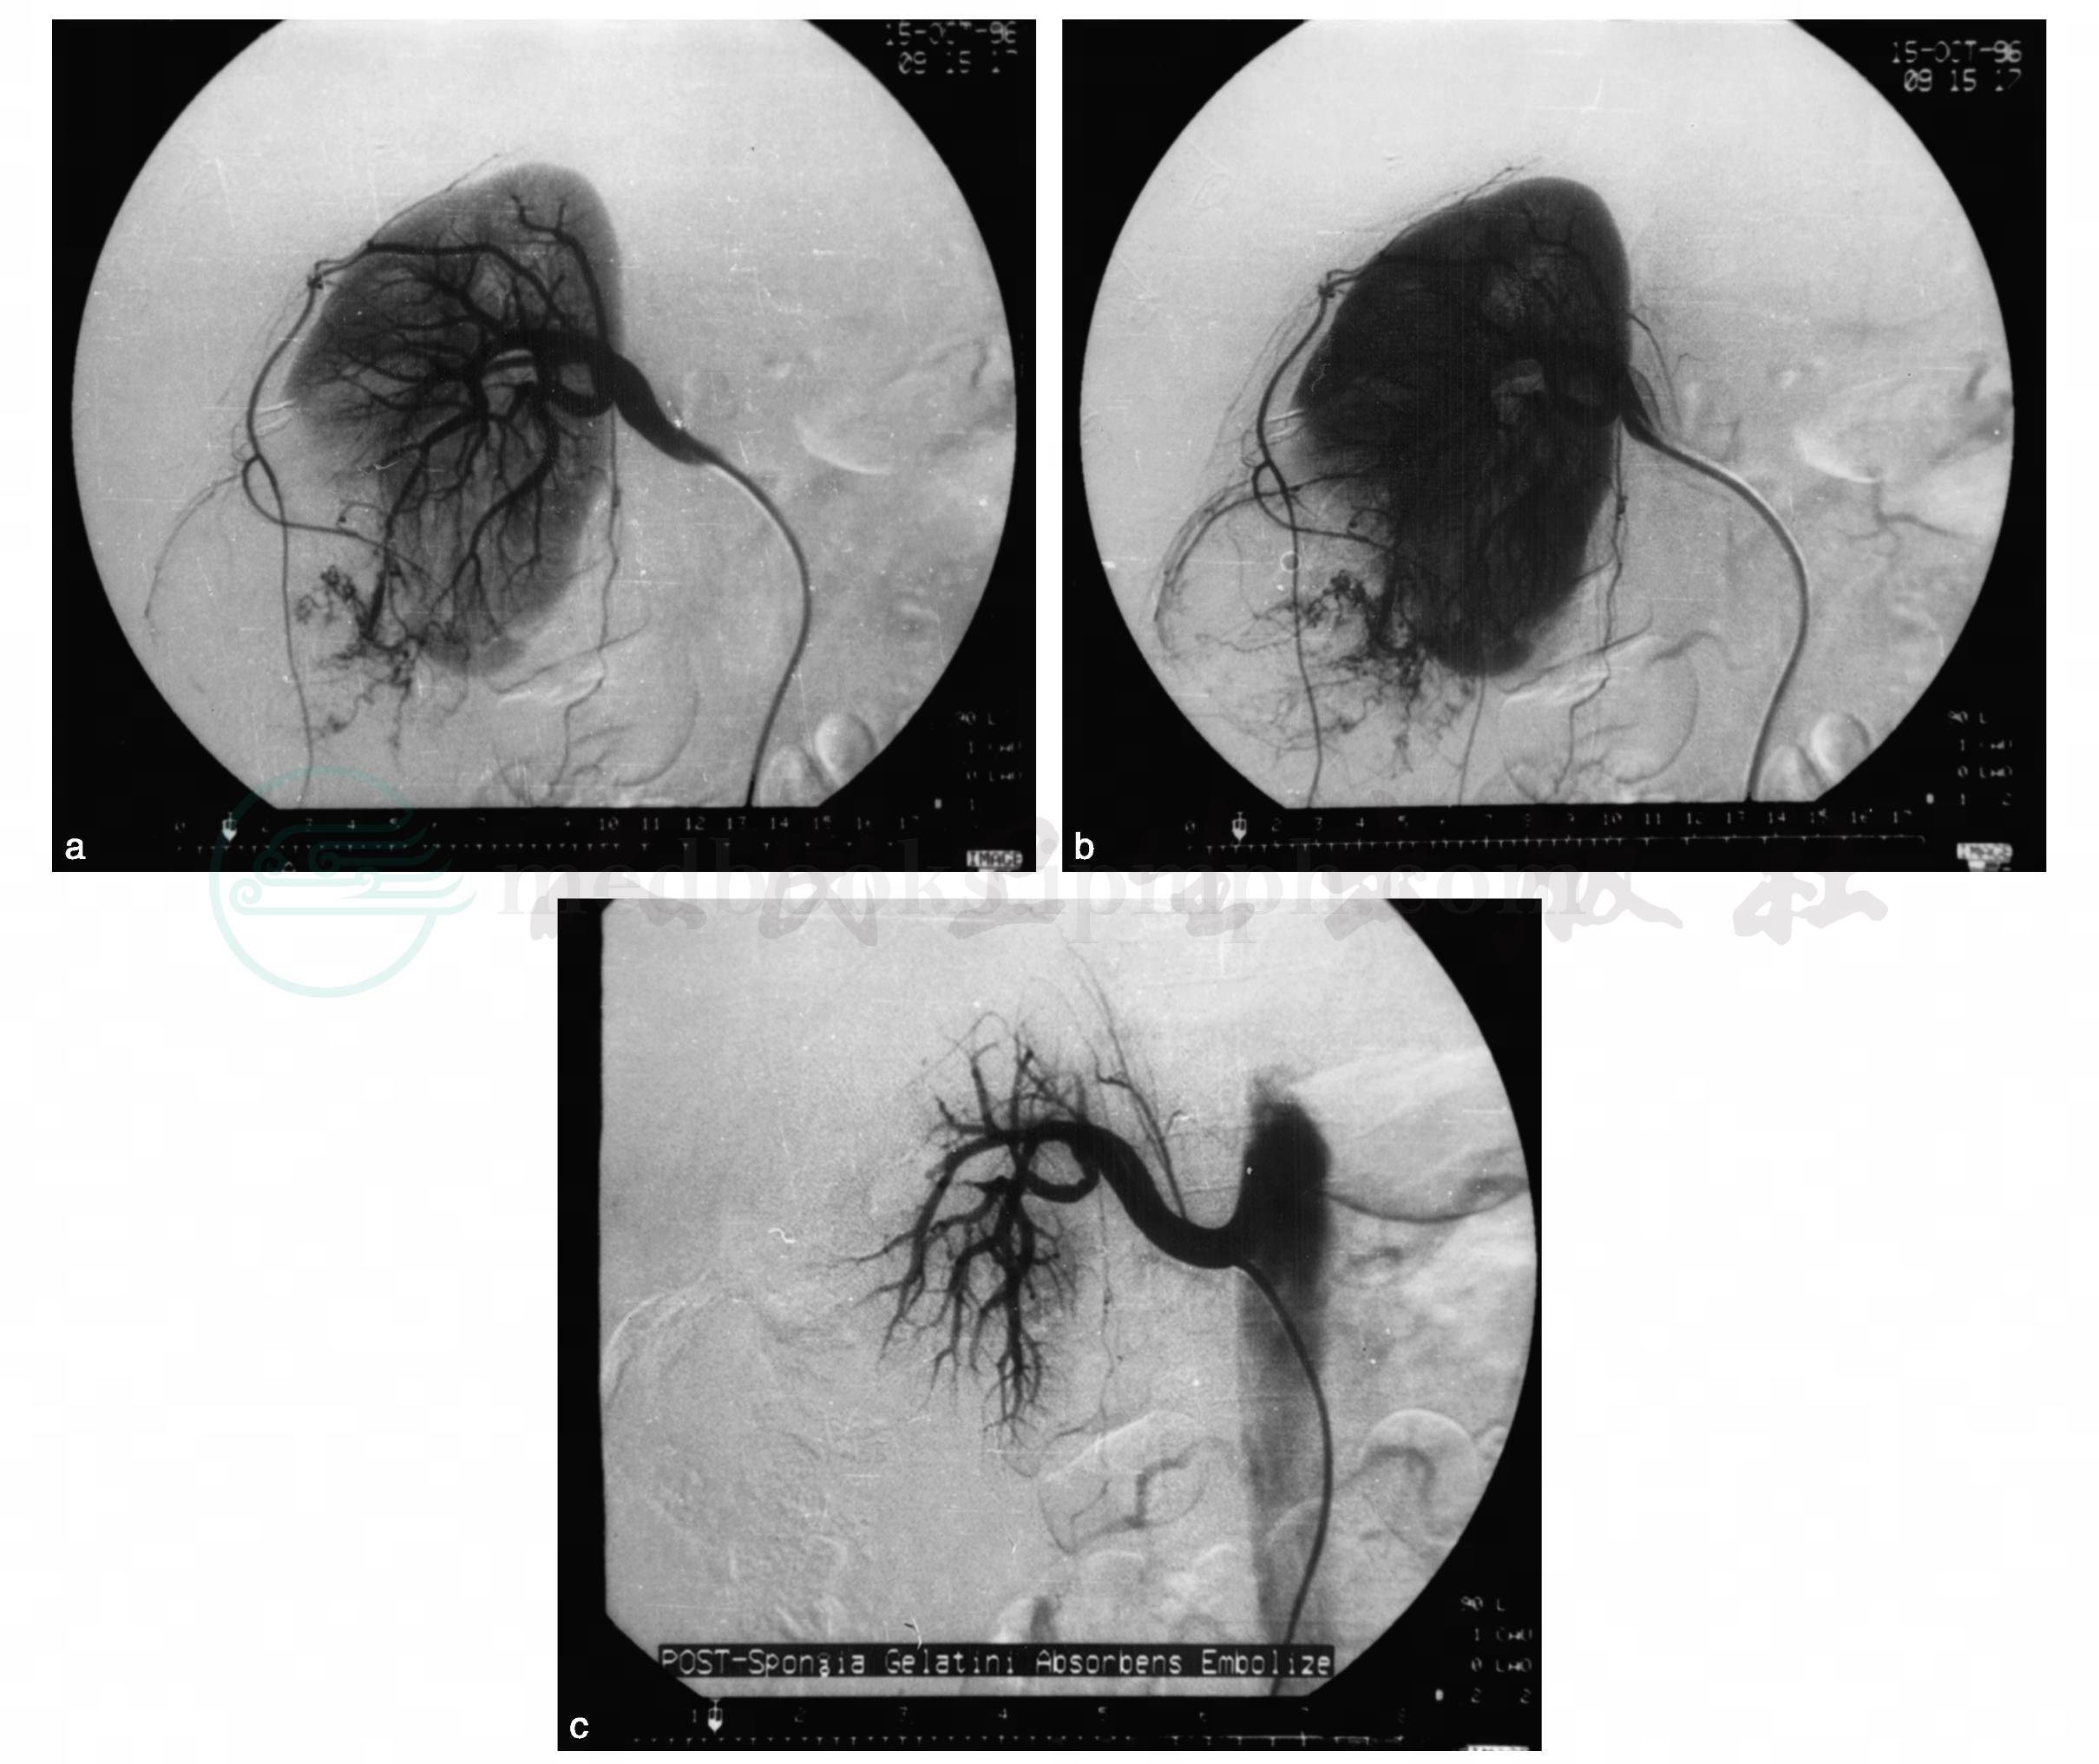

肾动脉造影主要显示肿瘤血管多少与形态,肿瘤所含血管成分越丰富,造影所示血管越多。肾血管平滑肌脂肪瘤比较有特征性的征象是:①肿瘤血管排列成旋涡状或放射状(图10);②供血动脉失去逐级变细的分支现象,呈现迂曲、多发的小动脉瘤样凸出或葡萄状的假动脉瘤样扩张(图11);③实质期肿瘤中可有多数境界较清楚的透明区(代表瘤中脂肪成分);④扩张血管分支排空延迟,静脉期呈葱皮样外观;⑤肿瘤与正常组织分界较清楚;⑥较大肿瘤或肿瘤自发破裂致肾包膜下出血,可显示肾包膜动脉移位(图12a~b)。

如肿瘤较大,估计难以切除或肿瘤自发破裂致肾周出血,可行DSA造影,同时行选择性动脉栓塞,栓塞后显示肿瘤供血动脉中断(图12c)。

图12 肾血管平滑肌脂肪瘤

a﹒选择性肾动脉造影(DSA)示右肾中下动脉向肿瘤供血,肿瘤血管迂曲,呈放射状排列;b﹒肿瘤破裂致肾包膜下、肾周出血,显示肾下极包膜动脉移位;c﹒肿瘤血管超选择性明胶海绵栓塞术后